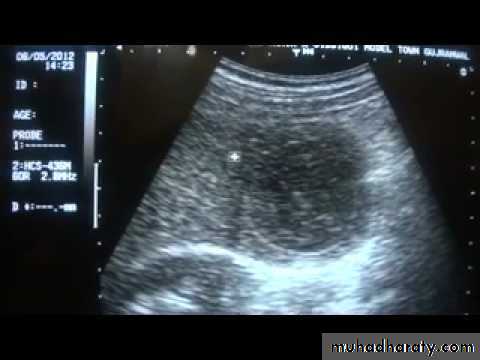

Focal masses ultrasound

Liver abscess: